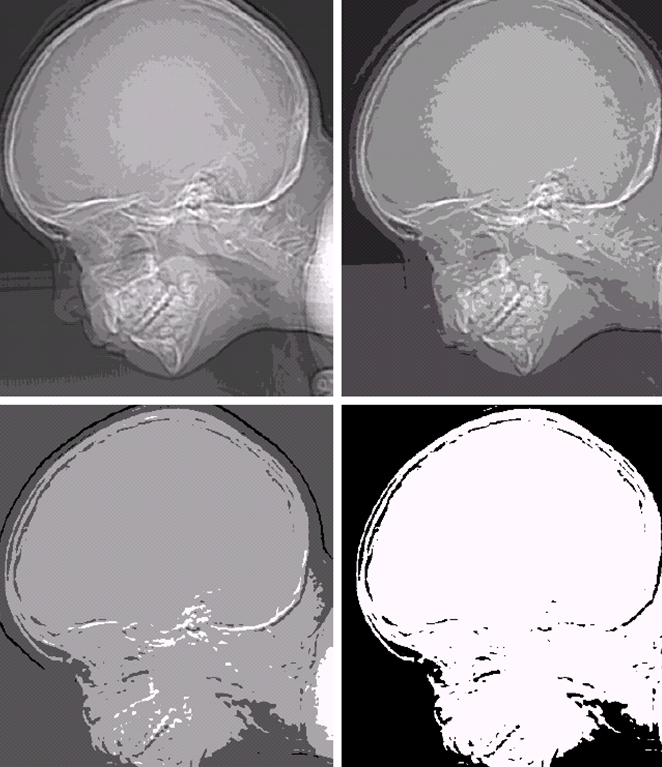

X射线

(c)头部CT

(d)电路板